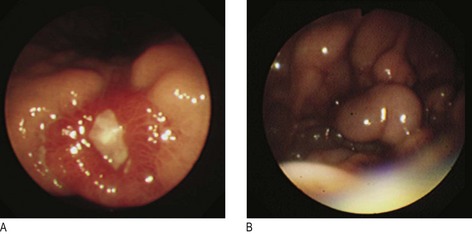

Fig. 8.13 Surgical stomas.

A, An ileostomy is usually in the right iliac fossa and is formed as a spout. B, A loop colostomy is created to defunction the distal bowel temporarily. It is usually in the transverse colon and has afferent and efferent limbs. C, A colostomy may be terminal, i.e. resected distal bowel. It is usually flush and in the left iliac fossa.